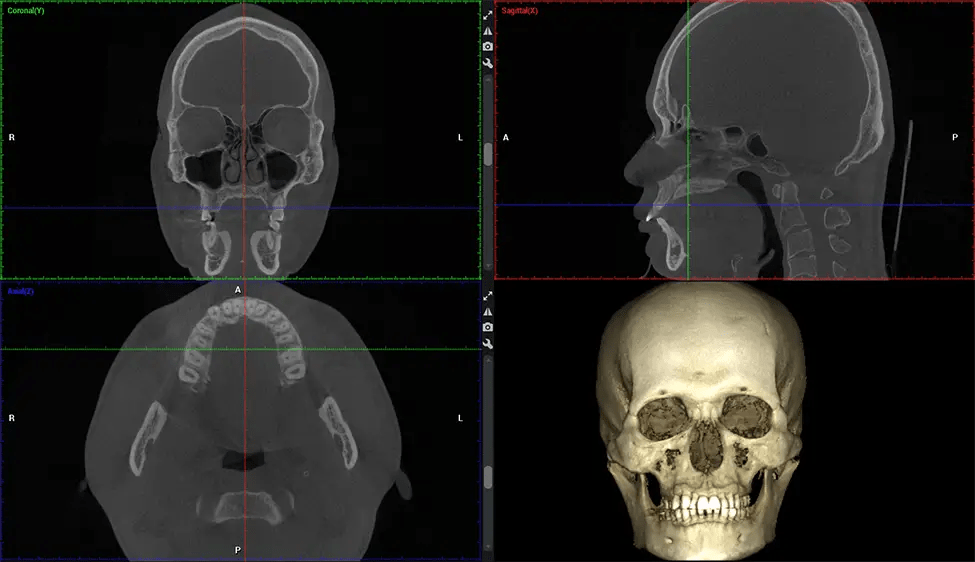

Cone Beam Computed Tomography (CBCT) is an advanced imaging technique used in dentistry and maxillofacial surgery to obtain detailed 3D images of the oral and maxillofacial structures. At Dr G Dental Studio, our CBCT scanners utilize a cone-shaped X-ray beam and a specialized detector to capture images from different angles. A computer then combines these images to create a 3D representation of the patient’s oral anatomy.

This 3D scan, called cone beam computed tomography, gives your dentist a more complete image of your oral anatomy and disease processes than a traditional X-ray. Unlike conventional X-rays, which capture a 2D image of your mouth from various angles, a 3D scan takes multiple digital X-rays for one image. It provides a complete view of your jaw, teeth, nerves, and soft tissues. This enhanced view allows dentists to detect minor issues not visible in traditional 2D scans, such as impacted wisdom teeth or bone fractures in the sinus cavity.

There are many benefits to using CBCT technology, especially compared to the traditional 2D X-ray format. One of the most significant advantages of CBCT scans is that they provide much more information than traditional X-rays. A scan lets your dentist see images from all angles of your jaw and mouth, including your sinuses, nasal cavity, cheekbones, and other surrounding areas. This added information helps your dentist craft a comprehensive treatment plan that addresses all aspects of your oral health.

The patient is first positioned in the CBCT scanner, which typically consists of a rotating arm that houses the X-ray source and a detector. The patient’s head is immobilized to ensure accurate image capture. The X-ray source and detector rotate around the patient’s head, capturing various X-ray images from multiple angles. As the X-ray source rotates, it emits the cone-shaped X-ray beam towards the detector. The detector captures the X-ray images, which are then processed by the CBCT software.

Planmeca Viso G7 CBCT ( Cone Beam CT Scan ) is designed to surpass the demands of industry leaders, specialists, and large institutions. It’s has a large ø25×30 cm sensor with four built-in cameras. It can capture unlimited volume sizes from a ø3×3 cm to a ø30x30cm volume capturing the skullcap through C7 on the cervical spine. The Planmeca Viso G7 offers the industry’s largest single volume scan of ø30×19 cm. It’s poised to handle advanced imaging modalities such as Planmeca ProFace® and Planmeca 4D™ Jaw Motion technology. The occipital head support allows an unimpeded view of facial tissue.